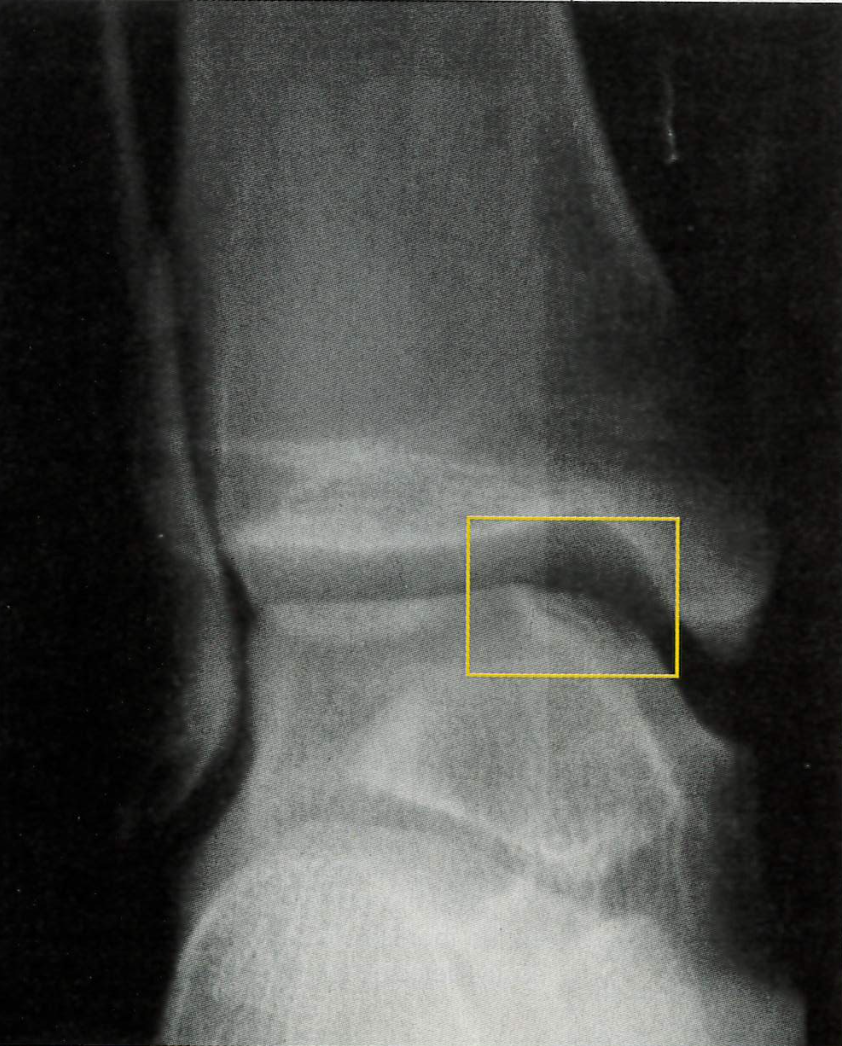

Radiographic findings. Fractures of the talar dome primarily occur on either the posterolateral or anteromedial aspect of the talar dome. Often the fracture is not visible on radiographs because of the curvature of the talar dome and because the area of the talar dome where the fracture occurs is usually not included on routine radiographs of the ankle. When the fracture is evident on radiographs, changes are located on either the lateral or medial aspect of the talar dome (Figure 5).

Management. When a fracture is evident on initial radiographs, immobilization and referral to an orthopedic specialist is warranted. Fragments of this fracture can become loose in the joint. Loose bodies in the joint can lead to episodes of sharp pain inside the ankle accompanied by a feeling that something is in the way. Because the fracture is generally not evident on radiographs, a talar dome fracture becomes the working diagnosis when the patient is slow to progress during or after a comprehensive lateral ankle sprain treatment program. For instance, if the patient has persistent pain inside the ankle with or without loose-body sensations during the program or after he returns to functional activities and follow- up radiographs are negative, the working diagnosis is a talar dome fracture and referral to an orthopedic specialist for further evaluation with a bone scan or MRI is warranted.

It is important to be able to distinguish a talar dome fracture from osteochondritis dissecans, in which a portion of the talar dome loses its blood supply (Figure 6). This type of avascular necrosis usually occurs during adolescence. The resulting bony lesion may remain asymptomatic and heal uneventfully with the return of adequate blood supply to the area, or it may present with symptoms compatible with a talar dome fracture (pain inside the ankle with or without loose-body sensations). The symptoms may develop insidiously or with any acute injury to the ankle.

Like talar dome fractures, osteochondral injury of the talus may not be evident on initial radiographs. When the lesion is evident, immobilization and orthopedic referral is appropriate. When the lesion is not evident on initial or followup radiographs, the symptoms and the age of the patient dictate whether an orthopedic referral for further evaluation with bone scan or MRI is warranted.